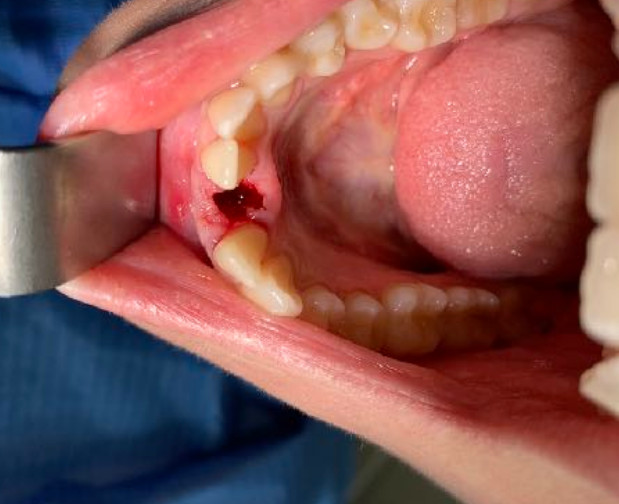

The density coding is the one adopted by Carl Misch and ranges from a maximum of D1 to a minimum of D5 for the least consistent bone. The density value is confirmed by the torque present at the time of tapping. With high torque values it is advisable to choose a tap and implant with a smaller diameter, for example diameter 4 mm. With gradually lower torque values it is advisable to increase the diameter of the implant compatibly with the thickness between the cortices.I remember that unlike current implant systems, the value of the emerging neck of the Tramonte implant is always and only 2 mm even when the overall diameter is 6 or 7 mm or even 8 or 10 mm.

The reduced diameter of the neck allows you to protect yourself from any peri-implantitis and significantly improves the speed of healing. In this case it was tapped with a diameter of 4 and a Tramonte implant with a diameter of 4 mm with 7 threads with short neck was inserted. The titanium used is always grade 4.

| Drill sequence: Lanceolate cutter only | Sequence of taps: tap diameter 4 mm |